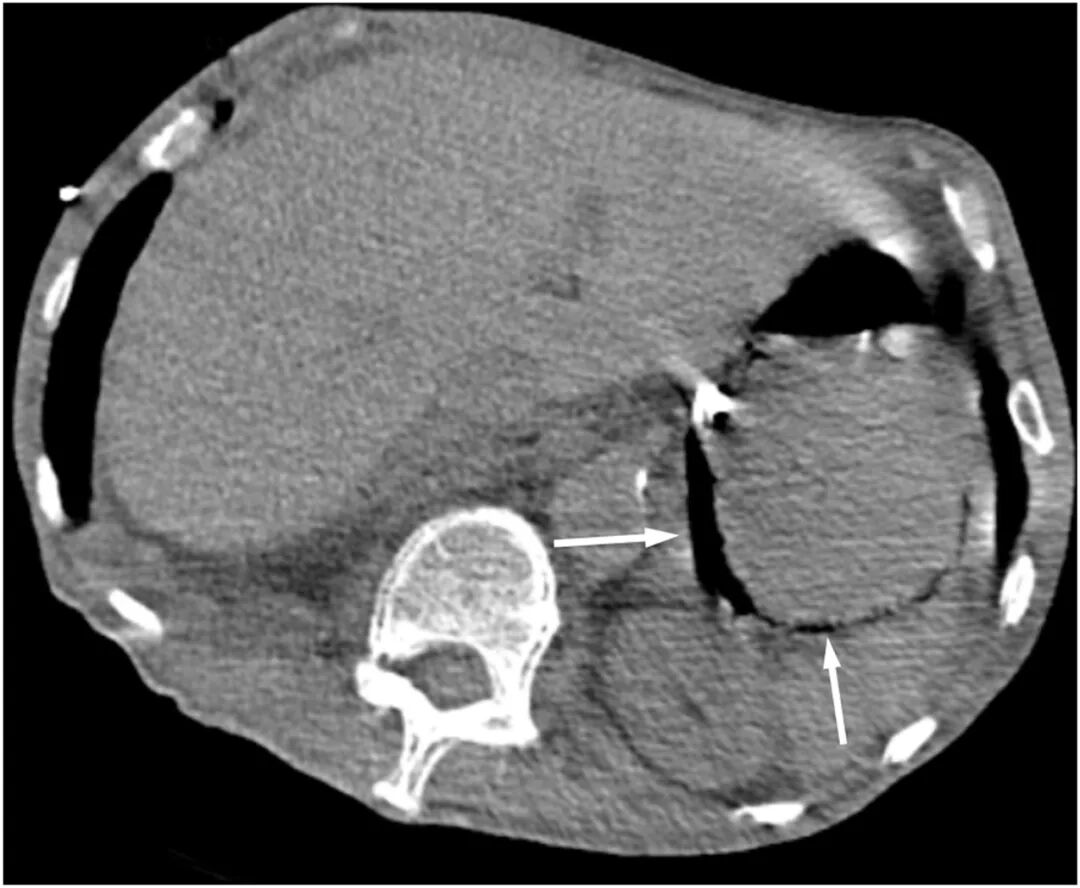

图4 腹部CT显示胃壁黏膜下积气(箭头)

胃壁内气体的存在是气肿性胃炎的关键影像学特征,通常可通过腹部CT得以明确。CT扫描能够清晰显示胃壁内的低密度线性影,有助于区分气肿性胃炎和良性胃气肿 。本病例中,在CT确诊前,通过床旁超声检查率先捕捉到了胃壁的“彗星尾征”伪像,这一发现为早期诊断提供了宝贵线索。“彗星尾征”通常与肺部和胆囊疾病相关。